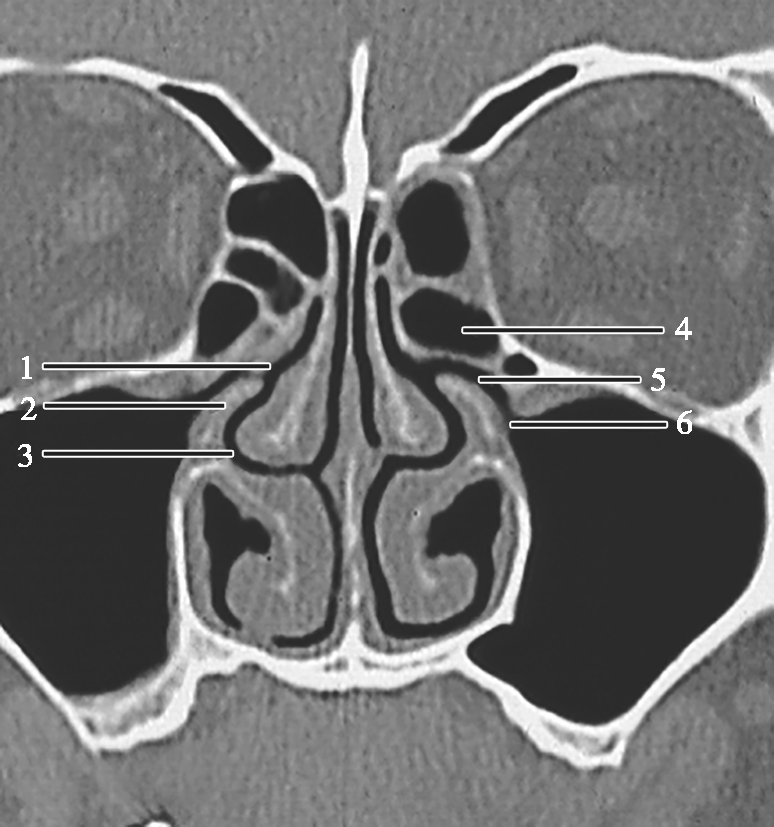

窦口鼻道复合体(ostiomeatal complex,OMC):由于纤维内镜生理性手术的需要,近一二十年来提出了窦口鼻道复合体的概念。窦口鼻道复合体并非一个独立的解剖结构,而是指前组鼻窦自然开口周围的区域,包括中鼻甲、钩突、半月裂、筛漏斗、鼻丘、筛泡、上颌窦自然开口等解剖结构(图1-3-2)。

图1-3-2 窦口鼻道复合体解剖

1.半月裂;2.钩突;3.中鼻道;4.筛大泡;5.筛漏斗;6.上颌窦开口